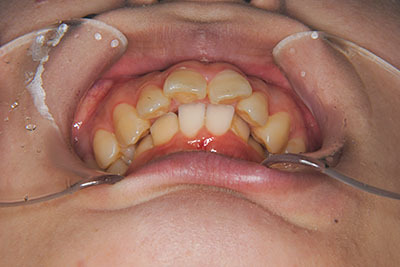

おとなの方でも矯正治療をあきらめないでください!

矯正歯科治療は子供の頃だけしかできない……

子供の頃に比べ大人になったら治療期間がすごく長い……

というようなイメージをお持ちではありませんか?

子供の頃に矯正治療を行う方が治療期間が短く済むというのは、確かですが、矯正治療は患者様の意識も重要です。

いくら歯が動き易くとも、本人がやる気でなければ効果は出ませんし、むし歯発生のリスクも高まります。おとなの方は顎の成長が終わっているため、治療の計画が立てやすいとも言えます。「もう大人だから…」とあきらめず、一度ご相談ください。